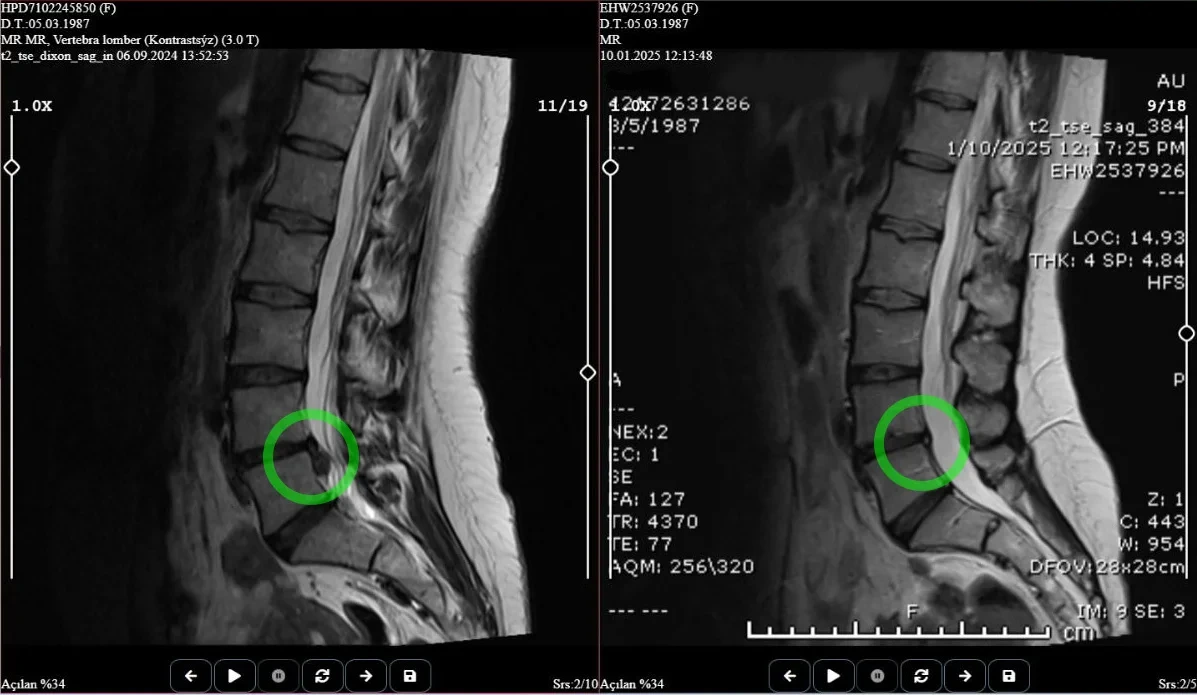

Ameliyatsız Bel Fıtığı Tedavisi

Cerrahi müdahaleye gerek kalmadan bel fıtığına etkili ve güvenli çözümler sunuyoruz

Nükleoplasti Tedavisi

Eklem ağrılarınızı hafifleten, hareket özgürlüğünüzü geri kazandıran tedaviler